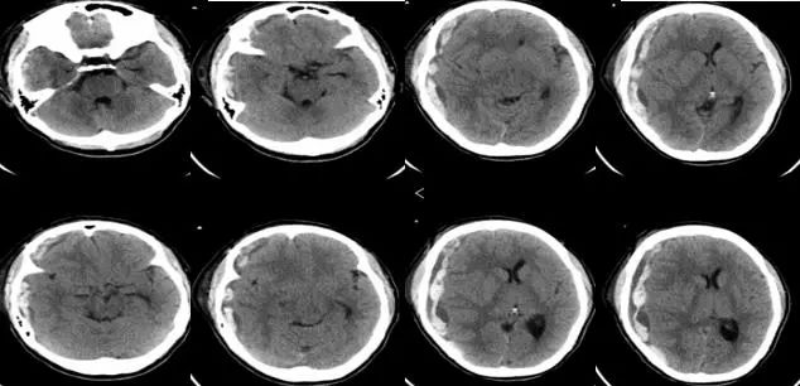

2024年4月20日11:30,王女士复查颅脑CT,提示右侧额颞顶部硬膜下出血较前增多,注意脑疝形成。随后患者出现意识下降呈昏迷状,双侧瞳孔等圆不等大,右侧直径约5.0mm,对光反射消失,左侧瞳孔直径约2.5mm,对光反射迟钝。神经外科廖小辉副主任医师受邀急会诊,并将该患者病情向罗洪海主任医师、黄小山主任医师汇报。

此时患者已脑疝形成,右侧瞳孔扩大,病情非常凶险,时间就是生命,因患者存在尿毒症,无尿,长期血液透析治疗,开颅手术及麻醉风险非常高,黄小山迅速组织我院麻醉科、重症医学科、肾内科等多学科讨论,决定急诊气管插管全麻下实施“右侧扩大翼点入路开颅硬膜下血肿清除术,去骨瓣减压术”,必要时麻醉同时进行CRRT治疗。手术由神经外科廖小辉副主任医师主刀,经过麻醉科医护人员的通力合作,2个小时后成功为王女士实施了开颅手术治疗。术后经神经外科二区及重症医学科医护人员的精心治疗,患者逐步康复,四肢活动自如,步行出院。

△ 术后CT。